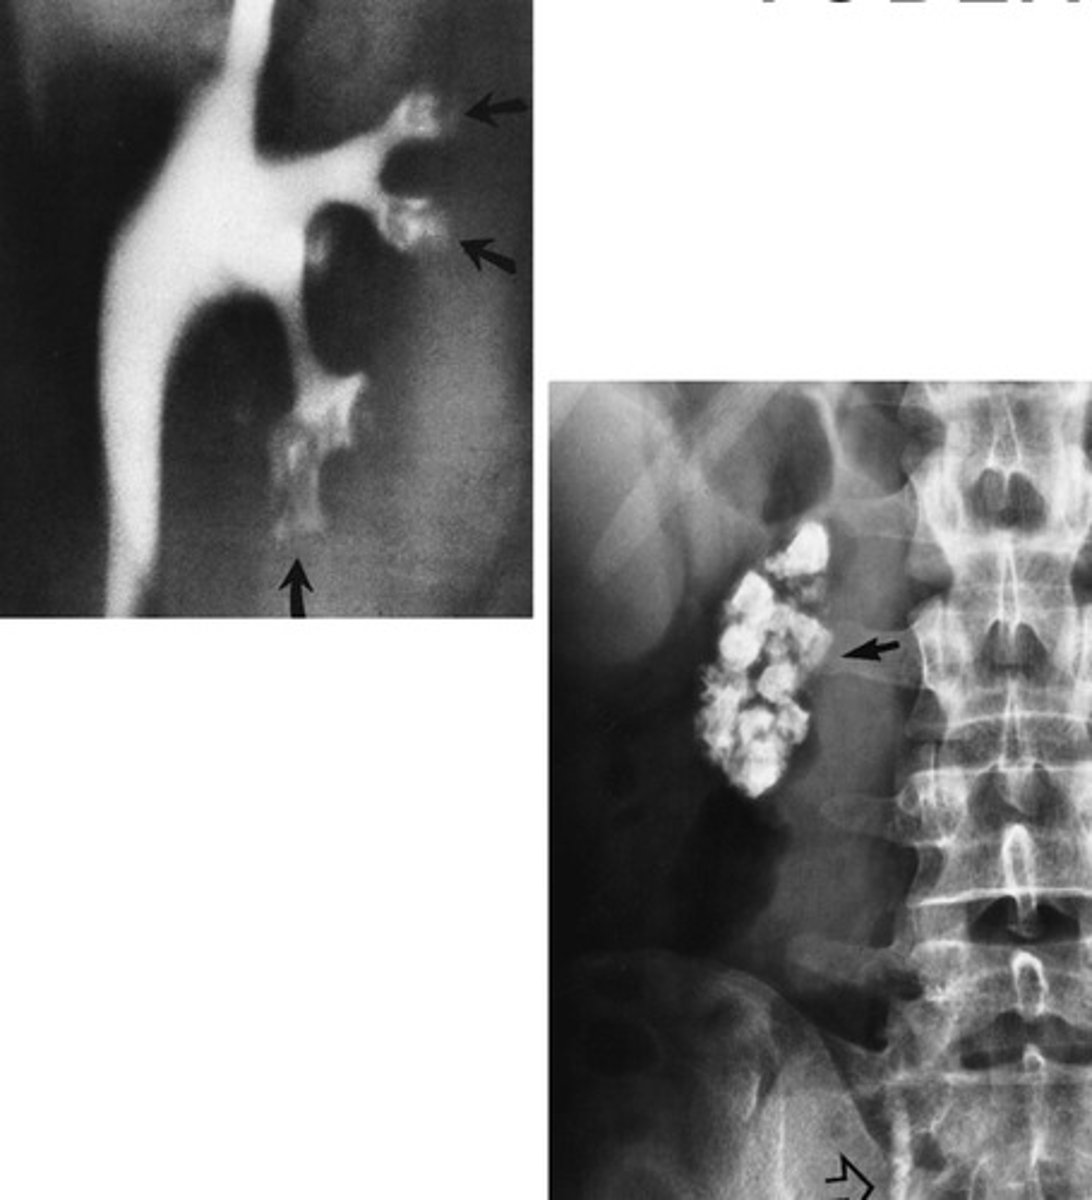

- Uteroceles

- "Cobra Head"

- With surgery

- What congenital anomaly refers to the cyst-like dilation of the distal ureter where it enters the trigone of the bladder?

- How does this pathology appear radiographically when the bladder is contrast-filled?

- How is this pathology treated?